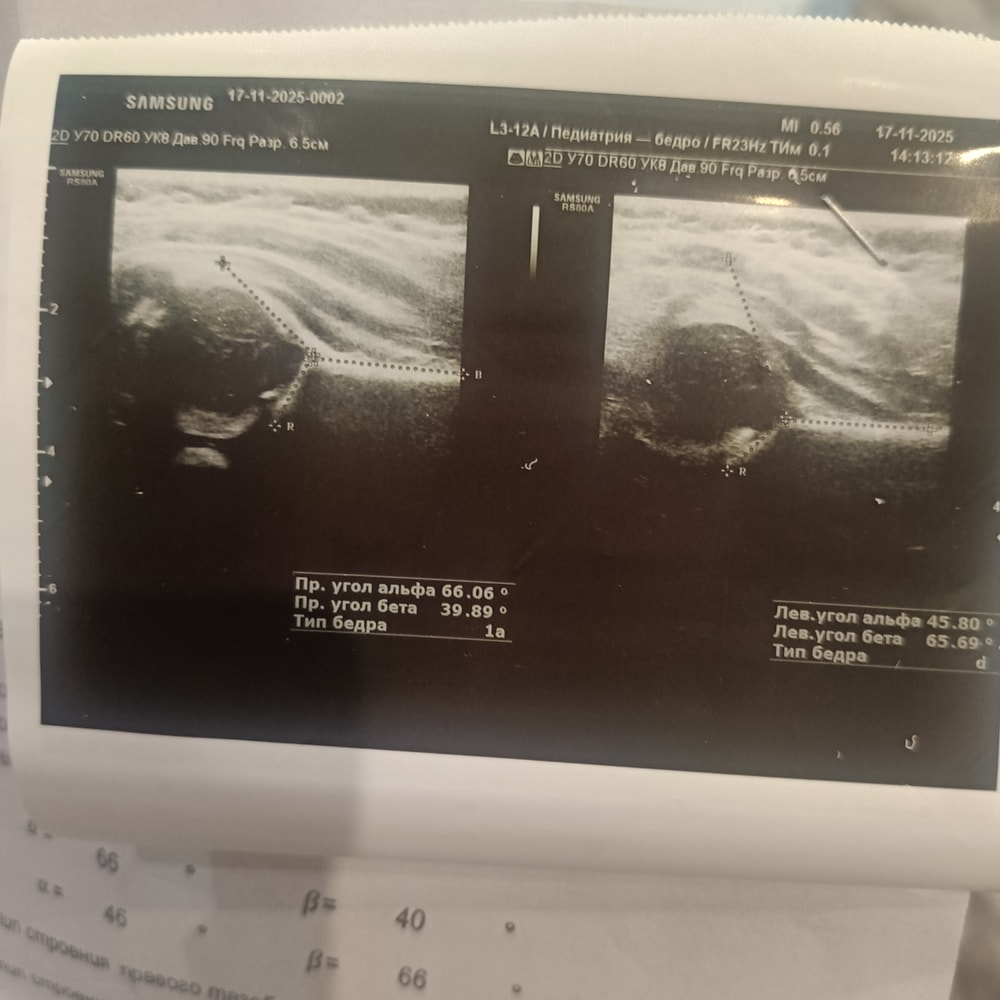

Добрый день. Может кто сталкивался с таким. Встали у опоры в 5,5 месяцев. Ходить начали в конце 8 месяца. Стали замечать что левую ножку он более загибает и косолапит ею когда ходит и ножки колесом (ну про жто я читала что нормализуется к 18 месяцам). И когда лежит он ее загибает. Витамин D принимаем. Если вы сталкивались с таким же как исправляли?